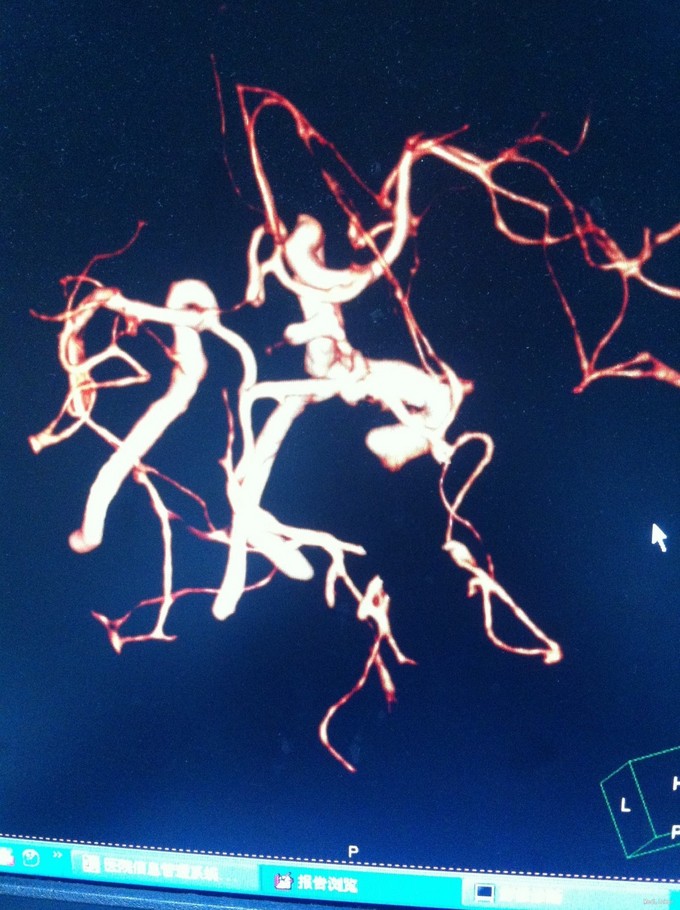

颈总动脉全程狭窄病例一例

动脉狭窄 颈总动脉狭窄

1、眩晕综合征 2、左侧颈总动脉狭窄